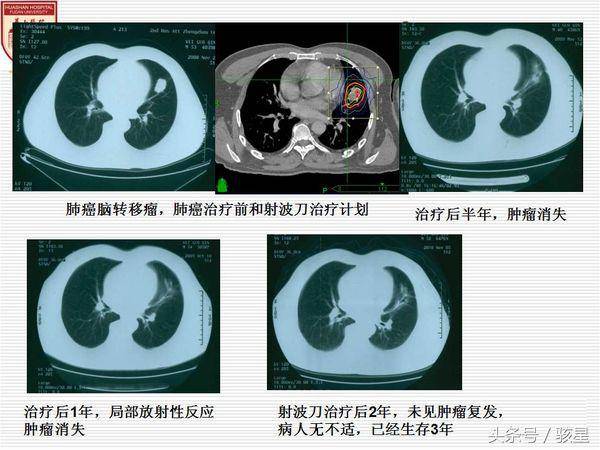

肺癌脑转移

肺癌转移